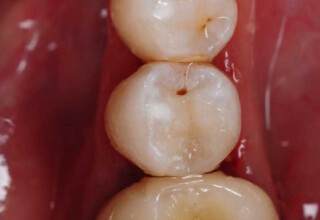

Restoration of a cracked molar with composite resin

Cracked teeth present a challenge in restorative dentistry both from the aspect of complexity of the restoration itself (usually large filings) and the necessary providings to avoid a complete fracture. The presented case demonstrates the simplest approach of a bonded direct restoration with composite resin. It is based on the principle of an adhesive filling that “holds” the remaining tooth structures “together”. The restored molar remained healthy for two years, then required a root canal and a crown was placed for maximum protection.